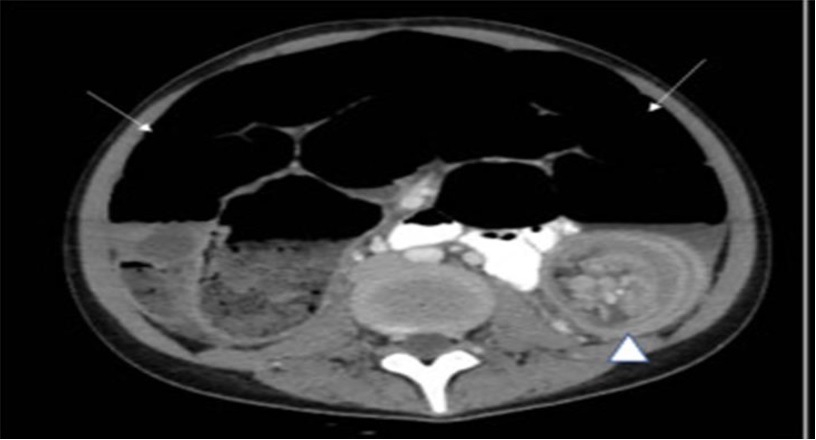

Cursa con deterioro rápido de estado hemodinámico y distención abdominal sin embargo sin datos de irritación peritoneal que requirió reanimación hídrica y uso de antibióticos con ampicilina/sulbactam, así como remisión a Unidad de Cuidados Intermedios. Fue valorada por cirugía pediátrica con indicación de tomografía de abdomen simple y contrastada con evidencia de imagen en diana o en «donut» (Ver imagen 1) sugestiva de invaginación intestinal secundaria. Es llevada de inmediato a laparotomía exploratoria abierta con hallazgos intraoperatorios (Ver imagen 2) de invaginación intestinal ileocecal secundaria a divertículo de Meckel con signos de isquemia y marcado edema, con dilatación de asa proximal, liquido cetrino libre en cavidad en moderada cantidad, adenomegalias mesentéricas sobre la región ileocolica, se realiza resección intestinal en un segmento de aproximadamente 20 cm de íleon distal a aproximadamente 20 cm de la válvula ileocecal con posterior anastomosis termino terminal, sin eventos durante la intervención.

Figura 1. Tomografía de abdomen.

Se señala en la imagen signo de «diana» secundaria a invaginación intestinal.